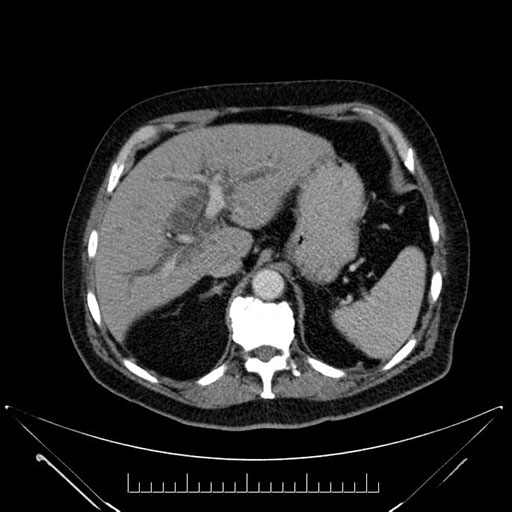

Imaging Analysis

Look through the patient's CT scan to identify any areas of concern for the necessary procedure.

Based on your CT findings, which issue(s) would give reason for "planned slowing down moment(s)" in this case?

Considering a standard Whipple procedure, what step(s) of the operation would you do differently in this case?